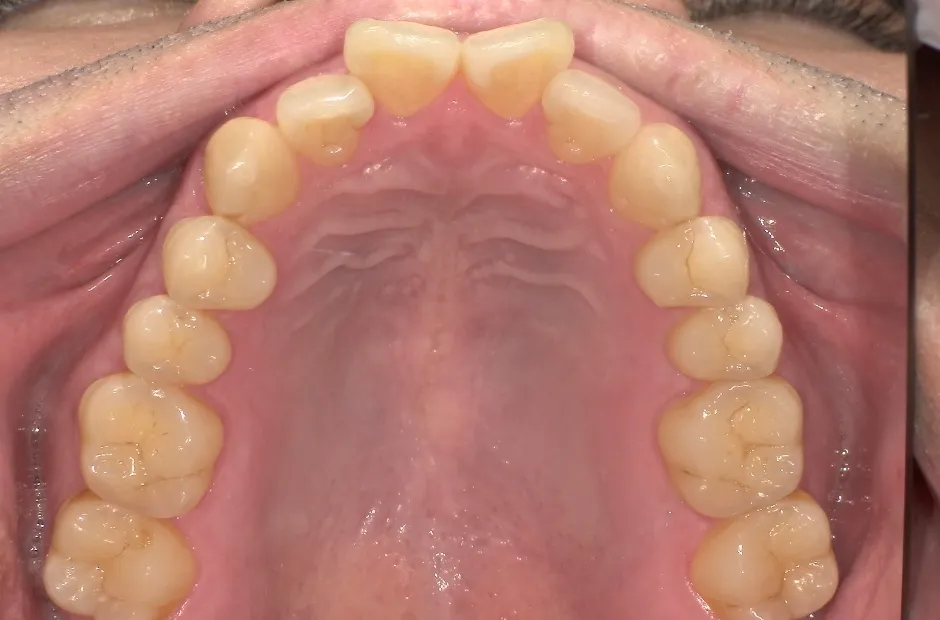

叢生

| 診断名・主訴 | 叢生 |

|---|---|

| 年齢・性別 | 43歳・女性 |

| 治療期間・回数 | 2年7か月 27回 |

| 治療に用いた主な装置 | 舌側矯正 |

| 抜歯部位 | 両顎4,4 |

| 治療費 | 100万円(税抜) |

| リスク・副作用 | 装置による違和感・疼痛・歯肉退縮・歯根吸収・虫歯のリスクなど |

治療前

治療後